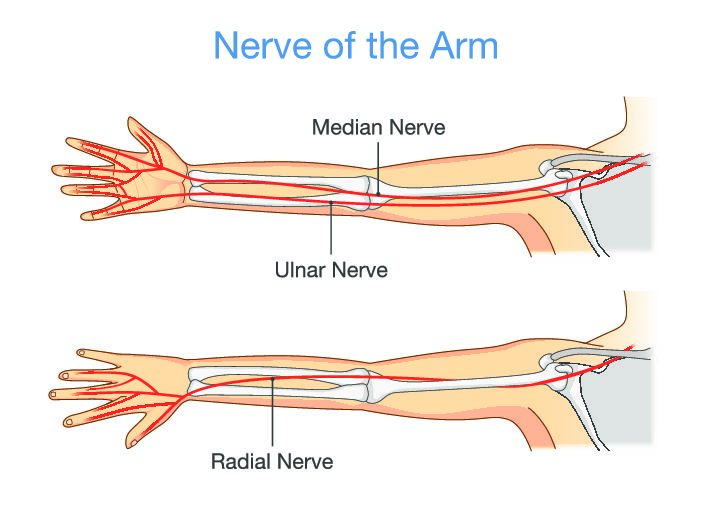

骑车人受伤:避免手部受伤和治疗策略

快速审查 Chiaramonte, R.、Pavone, P.、Musumeci, G.、Di Rosa, M. 和 Vecchio, M. (2022)。骑自行车者手部神经病变的预防策略、锻炼和康复:...